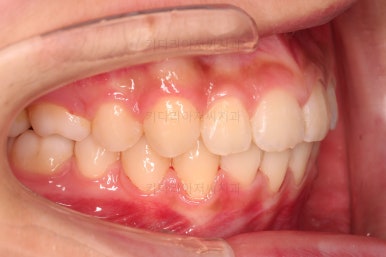

1. 초진 시 입안의 모습 평가

부산치아교정치과 키다리아저씨치과에 처음 내원했을 당시의 입 안의 모습입니다.

전반적으로 윗니가 나와있는 양상이고요.

앞니는 뻐드러져 있네요.

아래 앞니는 위로 솟구쳐 올라서 윗니 뒤쪽을 강하게 치고 있는 과개교합 양상이었고요.

위아래 앞니쪽이 삐뚤어져 있는 상태였습니다.

이번 학생은 입 안의 모습에서 보시다시피, 위아랫니가 앞뒤로 차이가 많이 나는 편이었는데요.

보통은 윗니가 튀어나온 돌출이라고 생각하고 부산치아교정치과 내원을 하시지만 이번 환자분도 아래턱이 작아서 문제가 시작된 경우였습니다.